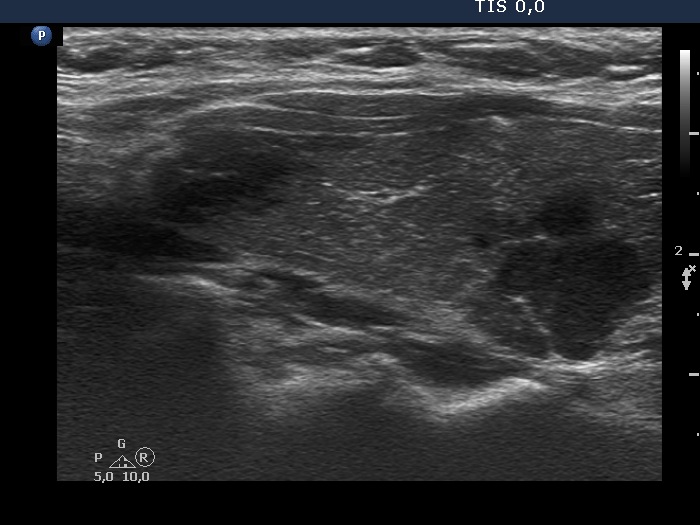

Ultrasonography. The thyroid was minimally hypoechogenic and had several discrete more hypoechogenic areas, including a cluster composed of multiple discrete lesions in the dorsal part of the left lobe. These lesions had irregular, partly lobulated, partly spiculated margins. However, the entire pattern corresponded to Hashimoto's thyroiditis.

Regarding the nodule borders the lesions presented partly lobulated, partly spiculated margins. However, these should not be held as pathological nodules, the discrete lesions are presentations of more active foci of Hashimoto's thyroiditis, which is an infiltrative process and therefore frequently has infiltrative, irregular margins.